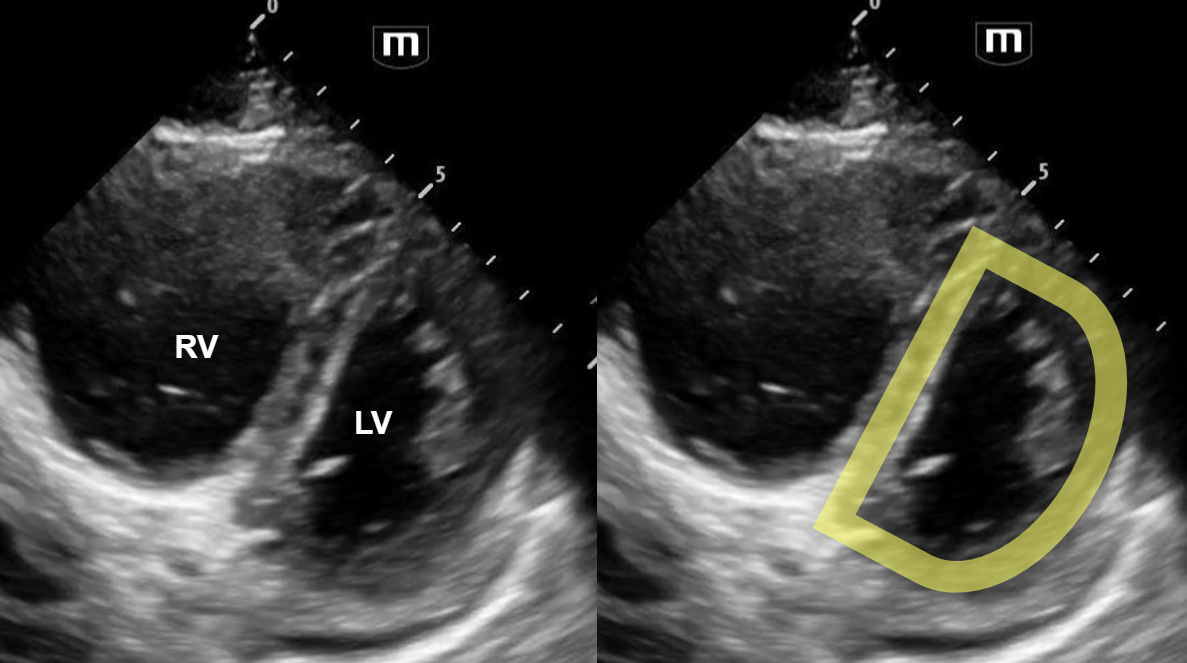

In this parasternal long view of the heart, we can see an effusion within the pericardial sac (pericardial effusion). This is represented by anechoic fluid that tracks anterior to the descending aorta. However, note that there is also fluid POSTERIOR to the descending aorta – this is a pleural effusion!

In this apical-4 chamber view of the heart, again we can see a pericardial effusion. Note that the right atrial wall collapses during systole!

The echocardiogram confirmed the presence of a large pericardial effusion with signs of early tamponade as well as a pleural effusion. The patient was admitted to the MICU.

Cardiac tamponade, pericardial effusions, and pleural effusions

·       It is important to be able to differentiate a pericardial effusion and a pleural effusion on the parasternal long view of the heart. Both look similar however there is one key differentiating factor. A pericardial effusion will be located ANTERIOR to the descending aorta, while a pleural effusion will be located POSTERIOR to the descending aorta.

·       The earliest sonographic finding of cardiac tamponade is right atrial collapse during early systole. As the pericardial effusion continues to grow, diastolic right ventricular collapse can also occur.